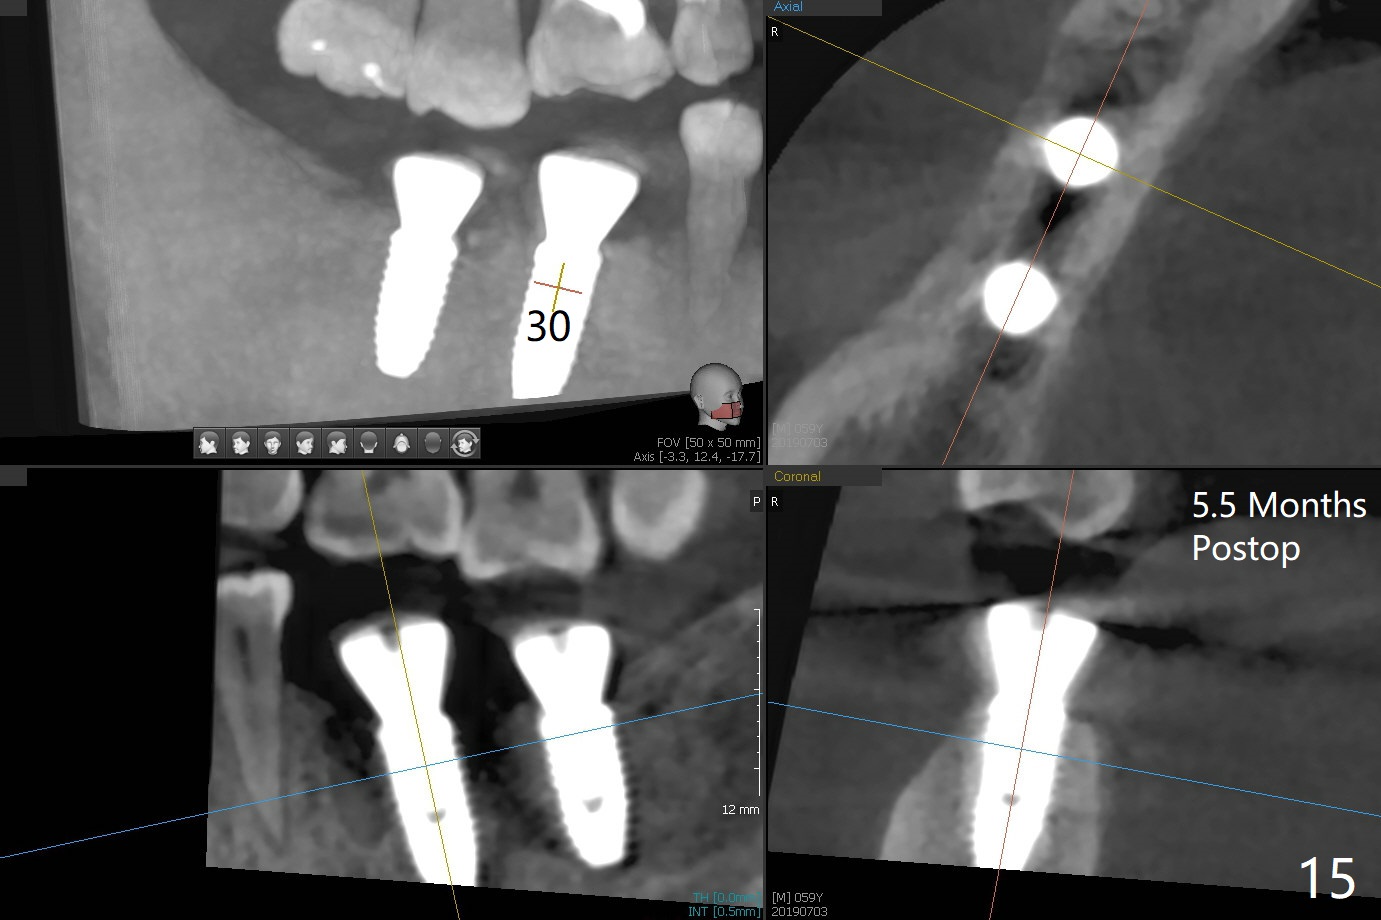

Abutment vs. Definitive One

After extraction of the tooth #30 with lingual subgingival fracture (Fig.1), the septum is fairly large (Fig.2 S). A bony vertical anchor pin (Fig.3 *) is inserted in the septum following pointed drill to to stabilize the guide during osteotomy and implant placement of #31. When the latter is finished, a fixture anchor pin is used at #31 as planned. A healing abutment is placed at #31 because of supraeruption of the tooth #2 (Fig.4,5), while a cementation abutment is placed at #30 (Fig.5) with autogenous bone (from drills) and allograft placed around it (*, Fig.6). Finally an immediate nonfunctional provisional is fabricated to keep the bone graft in place (Fig.7 P). The bone graft remains in place gel-like nearly 1 month postop (Fig.8). CBCT axial section shows that there is not enough space for mini implant placement at the tooth #2 (Fig.9). Restoration-induced intrusion will be conducted using the implants at #30 and 31 three-4 months postop. The buccal gingiva (Fig.10 *) is lingual to the provisional (P) nearly 1.5 months postop. When the provisional is removed, it appears that the mesiobuccal bone graft has lost (Fig.11). Two days later, the cementation abutment is loose and removed; the gingival cuff looks healthy (Fig.12). A 6.8x5 mm healing abutment is placed (Fig.13). In 2.5 to 3 months, abutments will be placed at #30 and 31. Splinted provisional will be fabricated over supraocclusion to intrude the tooth #2 with a stop on the left side. Surprisingly the patient agrees to intrude the tooth #2 with 2 mini implants 5.5 months postop (Fig.14,15). However, the miniimplants dislodged. Due to coronavirus, the implants are restored with heavy abutment and opposing tooth trimming 1 year 9 months postop (Fig.16). Magicore should have been placed instead.